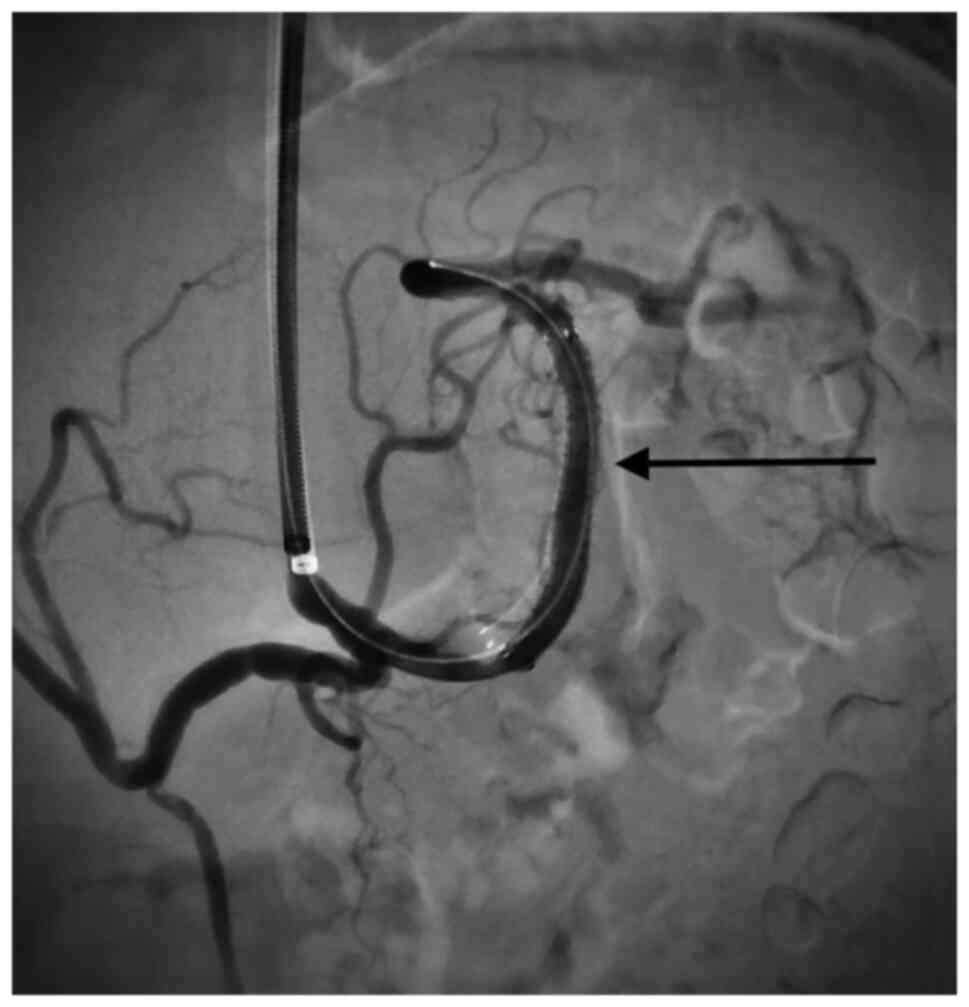

Visceral artery aneurysms are defined in this retrospective analysis as a true aneurysm in the celiac trunk (CT), superior mesenteric artery (SMA), inferior mesenteric artery, and/or their branches. Visceral artery aneurysms (VAAs) are rare and mostly asymptomatic., Rapid growth, size >2 cm, and pregnancy are risk factors associated with rupture. True visceral aneurysms are aneurysms are the result of weakening and thinning of the artery wall. Atherosclerosis, connective tissue disorders, infection (for example pancreatitis) and abdominal surgery are known risk factors for the development of VAA. Nowadays, conservative therapy, endovascular, and open surgery are the treatment options for patients with visceral aneurysms (VAA). During the last decade, endovascular repair of VAAs has been increasingly used (1-6). Catheter-based embolization or stent-graft placement are two major treatment options. Most VAAs originate from the splenic artery (SA) (60%) (Figs. 1 and 2), followed by the hepatic artery (HA) (20-50%) (Figs. 3 and 4). An origin from the superior mesenteric artery (SMA) (6%) (Figs. 5 and 6), the celiac trunk (CT) (4%) or other, smaller visceral arteries is considerably less common (7).

Anastomotic pseudoaneurysms and aortic aneurysms involving the visceral arteries were excluded. The decision to perform an open or endovascular repair was made after discussion in a multidisciplinary meeting (angiology, radiology and vascular surgery). All ruptured VAAs underwent intervention. Open repair was performed in general anesthesia as an aneurysmorrhaphy with or without vascular reconstruction by (direct end-to- end anastomosis or using a vein graft interposition). Endovascular treatment was performed in local anesthesia and consisted either of coilembolization or covered stent placement. If a stent graft placement was technically possible it was performed in order to maintain the vessel patency. If not, a coilembolization was performed.

Six aneurysms of SA, one aneurysm of the CT and one aneurysm of the HA were treated with ER (eight patients). Seven patients were treated with covered stents and one with coiling embolization. In total eight covered stents were implanted. Two patients with SA aneurysms and two patients with SMA aneurysms underwent OS. No allogeneic grafts were required. Three patients needed direct suture only and one a vein graft.